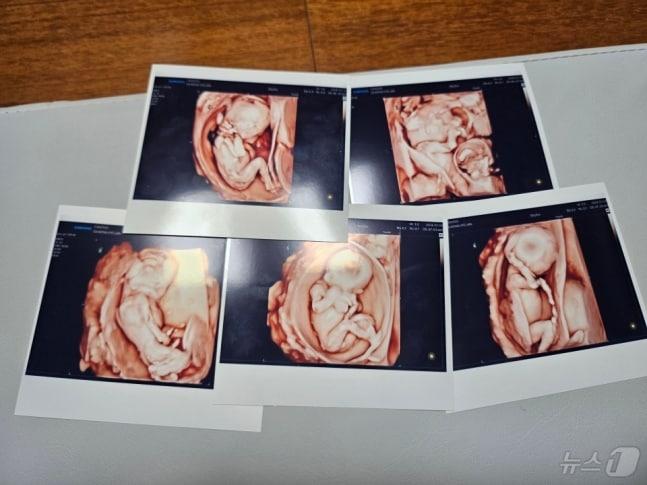

동두천 교육공무원 부부 다섯쌍둥이 순산20일 서울성모병원에서 다섯 쌍둥이가 탄생했다. 사진은 오둥이의 초음파 사진. (병원 제공)관련 키워드다섯쌍둥이이상휼 기자 "제주 4개 국제학교 학교폭력 사각지대"…김용태, 법 개정 대표발의남양주 농수산물 보관 창고서 불…1억5000만원 피해천선휴 기자 '전립선암 진단' 국내 개발 방사성의약품, 신약 허가South Korea Initiates Preparations for AI Basic Medical Care to Ensure Universal Access to High-qual...관련 기사'5월 결혼' 박은영, 쌍둥이 언니와 동반 화보…구분 어려운 붕어빵 외모 [N샷]李 대통령, 어린이대공원 '깜짝 방문'…줄 선 시민들과 '릴레이 셀카'이만기, 세쌍둥이 할아버지 됐다 "드디어 나도…아들 키울 때와 달라"장동혁 "정원오, 잘못된 건 네 탓…이재명의 일란성 정치 쌍둥이"청주 태아 '병원 41곳' 돌다 사망…"분만실 뺑뺑이 더는 안 된다"